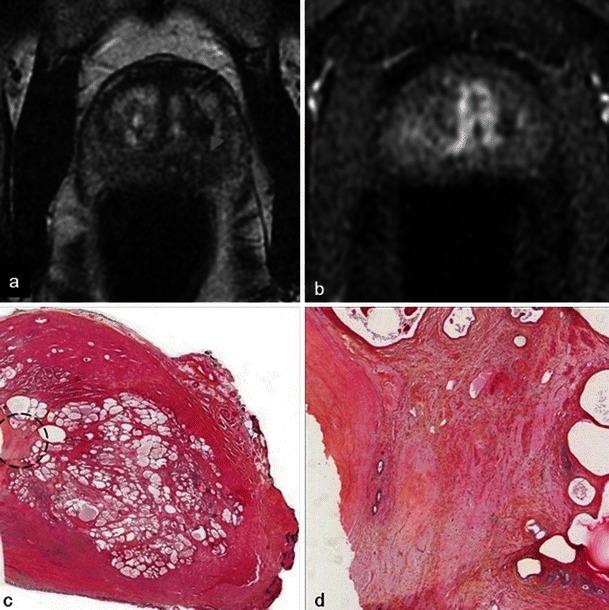

In this technique, a photosensitising agent is introduced intravenously, then activated by local laser illumination to induce tumour necrosis. Treatment efficacy is assessed by magnetic resonance imaging (MRI).

We illustrate specific post-treatment MRI aspects at early and late follow-up with pathological correlations.

• Dynamic phototherapy is a new and promising focal therapy for prostate cancer. • One-week MRI shows increased volume of the treated lobe and large, homogeneous necrosis area. • Six-month MRI shows significant changes of the prostate shape and signal. • Six-month MRI becomes "base line" appearance for further follow-up or monitoring.

• 动态光动力疗法是一种用于前列腺癌的新型且有前景的局部治疗方法。• 一周后的MRI显示治疗叶体积增大以及大片均匀的坏死区域。• 六个月后的MRI显示前列腺形态和信号有显著变化。• 六个月后的MRI成为进一步随访或监测的“基线”表现。